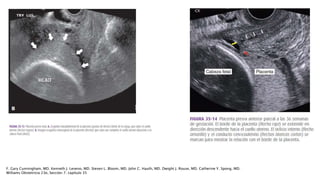

LOCALIZACIÓN MEDIANTE ECOGRAFÍA

Ecografía

transabdominal (96-

98%)

Ecografía transvaginal

Ecografía transperineal

(VPP 98%- VPN 100%)